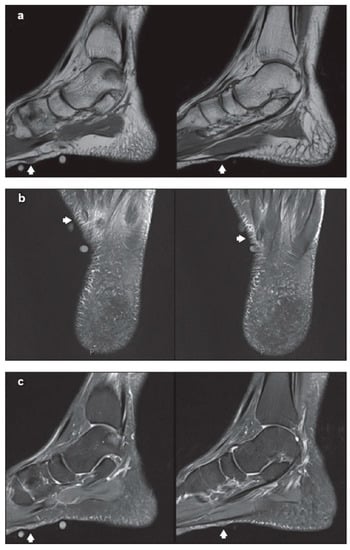

Using MRI, the normal plantar aponeurosis appears homogeneously hypointense on both T1-weighted and T2-weighted sequences [34]. On MRI, plantar fibromatosis emerges as a nodule that has low signal intensity on T1-weighted sequences and low-to-intermediate signal intensity on T2-weighted sequences (Figure 3). The aggressive nodules are seen as hyperintense on T2-weighted sequences, because of the high cellular matrix components [35]. For better detecting the small nodules, the administration of intravenous gadolinium-based contrast could be taken into consideration, notably where the hypointense small ones are hard to differentiate from low-signal aponeurosis on non-contrast-enhanced images [34]. For the aggressive and advanced forms, the MRI is excellent for showing how deeply affected is the aponeurosis [36].

Figure 3.

Non-contrast-enhanced magnetic resonance (MR) imaging showing two sub-centimetre nodules (arrows of a–c) along the inner band of the plantar fascia, on the left foot: (a) sagittal T1-W, (b) axial T2-W fat saturation and (c) sagittal proton density-weighted fat saturation MR images of the left foot. Source: Reprinted from Teo, F.; Mohamed Shah, M.T.; Wong. Clinics in diagnostic imaging. Singapore Med. J. 2019 [37] (Singapore Med. J. licensed under CC BY-NC-SA 4.0, no permission required).